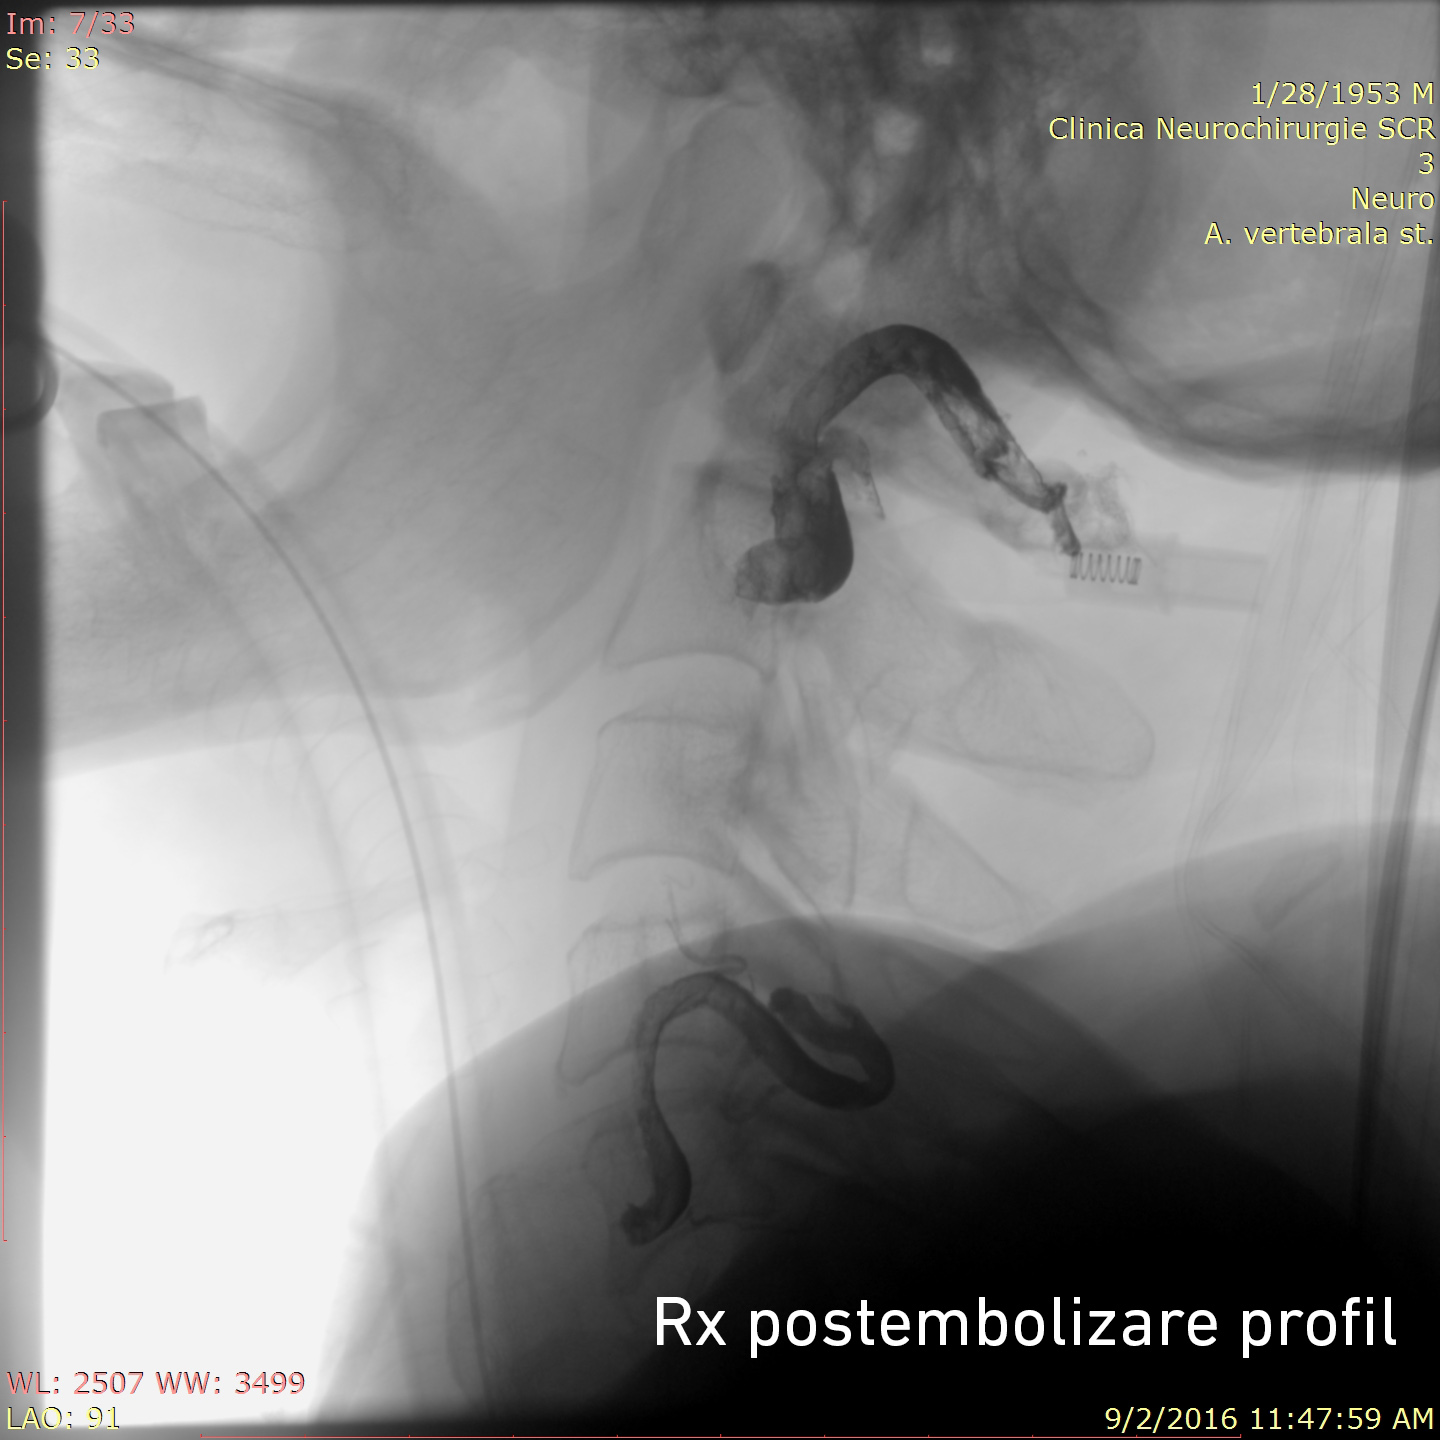

Tratamentul endovascular a fost realizat grație colaborării multidisciplinare între neurochirurgul-intervenționist Alexandru Șumleanschi, cardiologul-intervenționist Eugen Calenici și neuro-anestezisteziolog Iana Cotorcea. Embolizarea a avut loc în 2 etape sub anestezie generală : pe 15.07.2016 a fost ocluzată artera cervicală ascendentă stângă (trunchiul tireo-cervical) cu Onyx și pe 02.09.2016 a fost realizată ocluzia arterei vertebrale stângi (segmentul V2-V3). Toate obiectivele propuse înainte de operație au fost realizate cu succes. Starea pacientului s-a ameliorat după embolizare: au dispărut acufenele, au diminuat durerile nevralgice, ceea ce a permis diminuarea tratamentului neurotrop. Spre deosebire de chirurgia clasică, pacientul a necesitat timp redus de spitalizare și recuperarea după embolizare a fost rapidă.